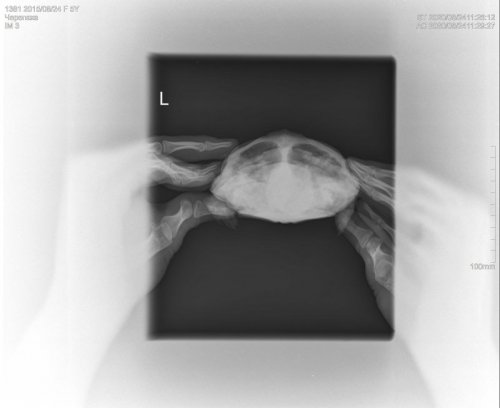

georgiy Ваше имя: Георгий Локация: Россия,г. Набережные челны Опубликовано: 24 августа 2020 Автор Опубликовано: 24 августа 2020 Здравствуйте,сделали рентген.

Консультанты moth Ваше имя: Мария Локация: Москва Опубликовано: 24 августа 2020 Консультанты Опубликовано: 24 августа 2020 @Podolnyi

Podolnyi Ваше имя: Подольный Константин Локация: Украина, Днепр Опубликовано: 25 августа 2020 Опубликовано: 25 августа 2020 У черепахи сильный метеоризм. Для более ясной картины должен быть правый латеральный снимок.